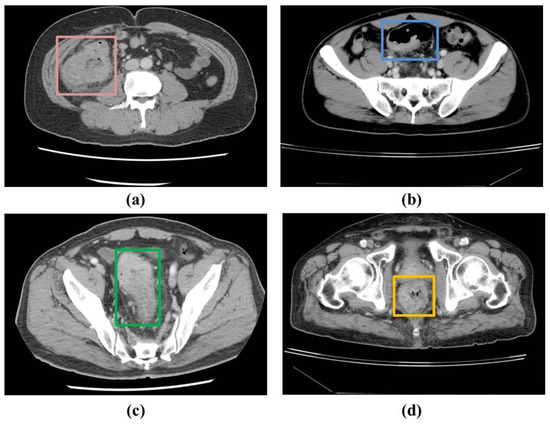

Based on Table 2, it is observed that RetinaNet outperformed YOLOv3 with a precision of 99%. However, YOLOv8 showed the best performance with 96% sensitivity and a 97% F1 score. The model could detect most of the CRC lesions in CT images. Moreover, Figure 5 shows a comparison of a few outputs produced by all three models with the provided ground truths. It can be observed that YOLOv8 has better localization accuracy with better confidence.

Figure 5. Slice-wise testing showing CRC lesions localized via different models with confident scores, where the first column represents the ground truth, and second–fourth columns show the bounding box for the localized CRC region as predicted by the different models. The absence of the bounding box shows the inability of the model in localization.